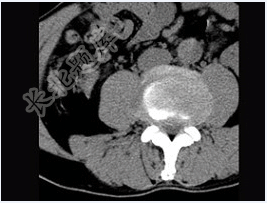

- 单项选择题男,45岁,腰痛,请结合所提供图像,选择最佳答案( )

A、前纵韧带钙化

B、椎间盘膨出

C、椎间盘突出

D、腰椎骨质增生

E、椎间盘未见异常